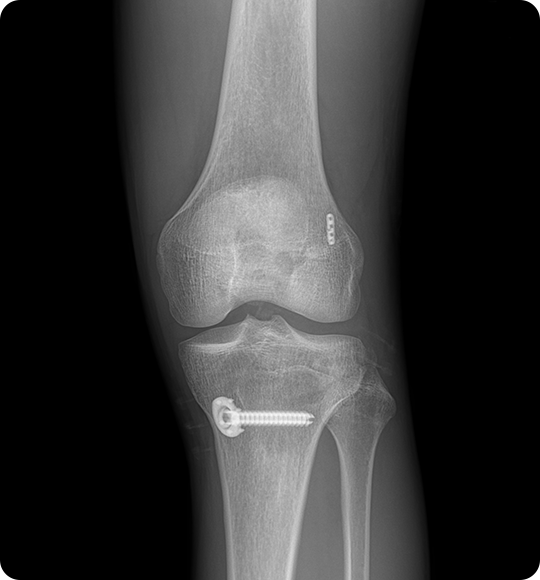

이 수술은 끊어진 인대를 봉합하는 것이 아니라

자가건(햄스트링건, 슬개건 등) 또는

인공건을 이용해 새로운 인대를 이식하게 되며,

재건을 통해 통증을 줄이고 무릎 기능을 되살립니다.

인대를 뼈에 단단히 고정 후,

관절 내 위치와 장력을

확인하고 봉합합니다.